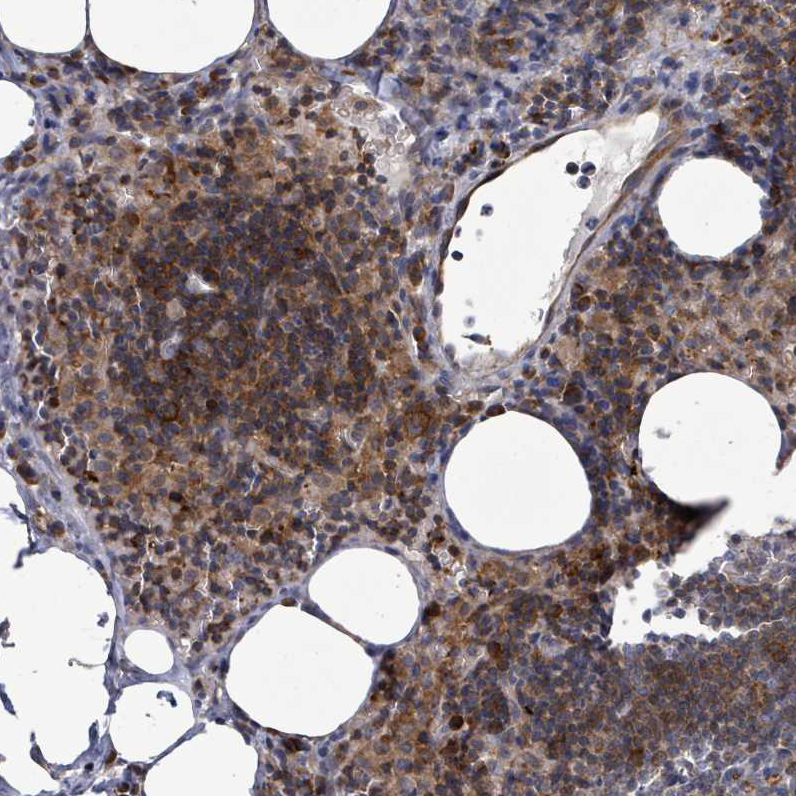

Immunohistochemical staining of human lymph node shows moderate to strong positivity in lymphoid cells.